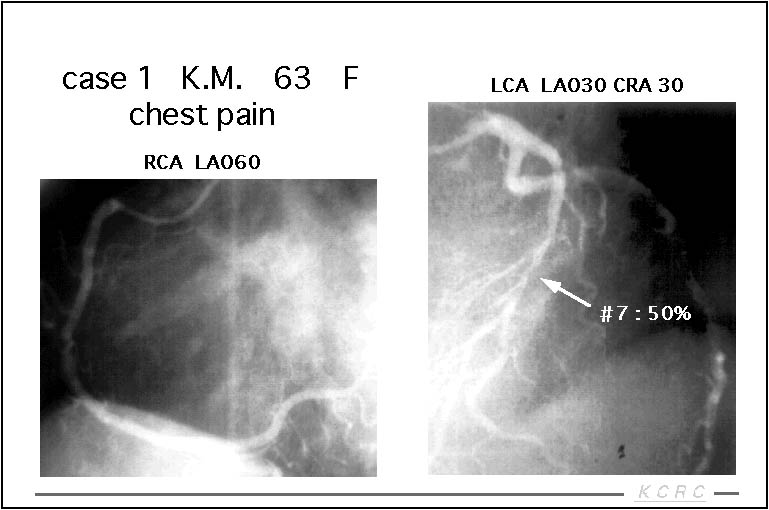

症例を呈示します。胸痛があり冠動脈造影を行った結果、LADに50%の狭窄を認め、虚血の有無の評価の目的でシンチを行いました。

【スライド7】

負荷像、安静像とも血流の低下は認められず、内服治療で経過観察となりました。